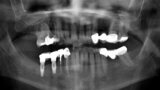

Fig. 2. Radiografía panorámica previa a la intervención quirúrgica.